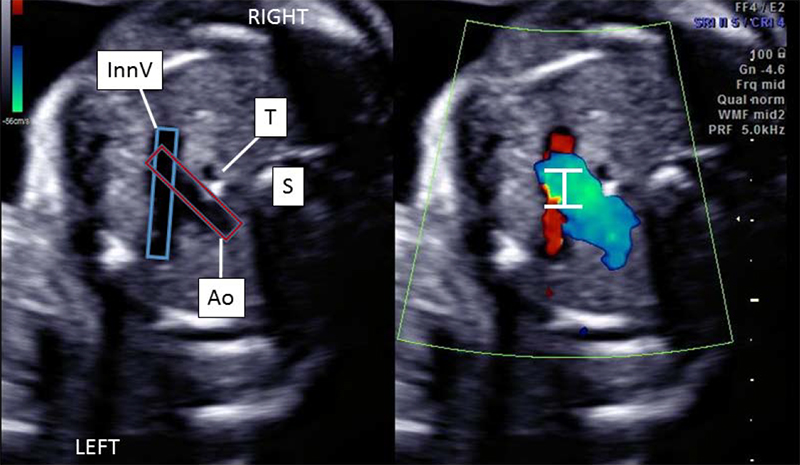

The team in the Fetal Cardiology Program at the Colorado Fetal Care Center at Children's Hospital Colorado, modified the SVC/AAo technique to improve the examination of fetal arrhythmias and evaluating fetal arrhythmias. They simultaneously recorded the pulsed wave Doppler signals in the innominate vein (InnV) and transverse aortic arch (Ao) from an axial view of the fetal thorax.

By employing a four-chamber view in a horizontal position, the InnV is easily identified by sweeping cephalad to the three-vessel trachea view. The InnV is located immediately superior to the transverse arch, and can be positioned in parallel to the ultrasound beam for clear and precise spectral Doppler sampling of the venous A-wave signal.

When the Doppler sample volume is widened, blood velocities in both the InnV and the Ao can be simultaneously recorded. (See Figure 1.)

The InnV/Ao method provides a near 0-degree angle of insonation of the InnV to optimize visualization of the retrograde atrial systolic flow. (See Figure 2 for fetal arrhythmias detected with the method.)